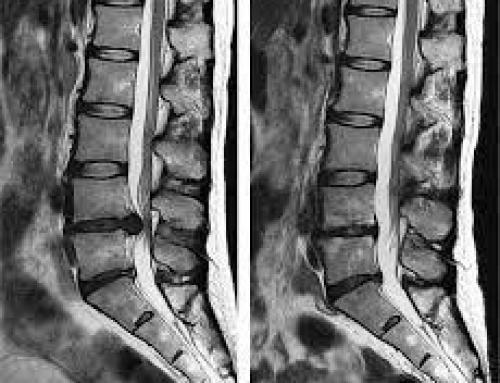

Ahora bien, ¿qué es la hernia discal? Se define como el desplazamiento localizado o focal del material del disco intervertebral más allá de los límites que lo delimitan. Con esta definición, todo debería entenderse un poco más fácilmente, pero, ¿tienes claro qué es exactamente el disco intervertebral? No te preocupes.

Cuando nos referimos a él, lo hacemos a la estructura que está situada entre cada una de las vértebras y que posibilita que la columna pueda flexionarse, así como soportar el impacto de nuestra vida diaria (caminar, correr, saltar, sentarnos, levantarnos…). Un disco intervertebral estará dividido tres dos partes bien diferenciadas:

- Hernia discal lumbar: Esta afectará a la zona baja de la espalda. Es la más habitual. Por suerte, en general, su recuperación es favorable, aunque requerirá de paciencia.